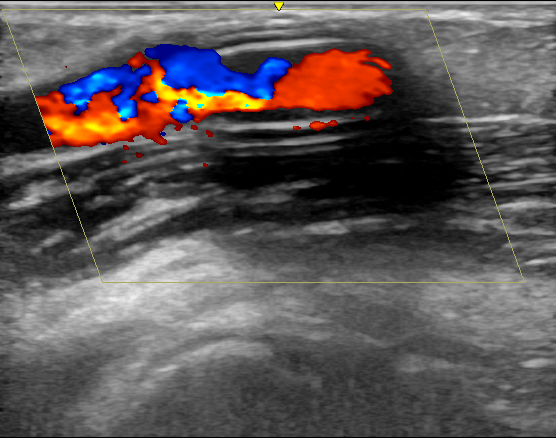

【覆膜|肾脏内科实施陕西省首例超声引导下透析通路支架植入术】近日 , 西安交通大学第一附属医院肾脏内科透析通路团队为一位人工血管内瘘狭窄的患者成功实施了超声引导下覆膜支架植入术 , 这是陕西省首例在超声下进行的此类手术 , 标志着西安交大一附院透析通路介入治疗技术的又一次提升 。 患者为男性 , 55岁 , 诊断为慢性肾炎 , 慢性肾功能衰竭 , 使用左前臂人工血管内瘘规律透析1年 。 该患者此前因为人工血管内瘘狭窄曾接受两次经皮静脉球囊扩张术(PTA) , 但术后狭窄很快复发 , 对于这种狭窄容易复发且单纯PTA效果不佳的患者 , 覆膜支架植入术是比较好的解决方法 。 经过充分的术前准备和一个小时的手术 , 肾脏内科杨世峰副主任医师及其团队成功为该患者实施了超声引导下覆膜支架植入术 , 术后患者人工血管内瘘血流恢复通畅 , 透析过程中血流量充足、静脉压正常 , 达到了较好的手术效果 。

血液透析通路是尿毒症患者的“生命线” , 目前尿毒症患者最常用的透析通路是自体动静脉内瘘和人工血管内瘘 。 然而内瘘无法避免的并发症就是狭窄 , 长期高速的血流会引起血管内膜反应性增生 , 导致内瘘管腔狭窄和血流量不足 , 影响透析效果 , 狭窄严重时导致内瘘闭塞、血栓和失功 。 处理动静脉内瘘狭窄最有效的方法就是PTA , 通过血管腔内治疗的方法解除狭窄 , 具有创伤小、恢复快的优点 。 然而部分病例单纯PTA后狭窄容易短时间内复发 , 对于这些病例覆膜支架植入是较好的解决办法 。 传统的支架植入术是在DSA造影下进行 , 而超声引导下介入手术是近几年新兴的技术 , 超声引导具有方便、无辐射损伤 , 无造影剂损害、可显示闭塞病变等优点 , 特别适合动静脉内瘘等外周血管的介入治疗 。